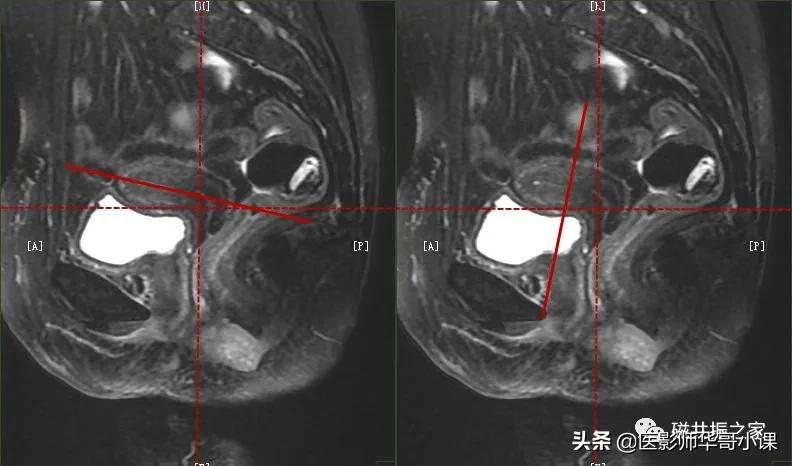

在冠状位和矢状位上定位,在矢状位上找到显示子宫全景最好的层面,如需了解宫颈病变,使定位线垂直于宫颈管长轴(图A),如需了解子宫内膜病变,使定位线垂直于子宫内膜长轴(图B)。在冠状位调整角度使两侧对称扫描,扫描范围上至子宫上缘下至耻骨联合,需包括整个病变范围,如视察转移性病变需加大扫描范围。

在横轴位和矢状位上定位,在矢状位上找到显示子宫全长最好的层面,如需了解宫颈病变,使定位线平行于宫颈管长轴(图A),如需了解子宫内膜病变,使定位线平行于子宫内膜长轴。在横轴位上找到显示子宫最大的层面,使定位线平行于当前子宫内膜长轴,扫描范围包括整个子宫及两侧附件,需包括整个病变范围。